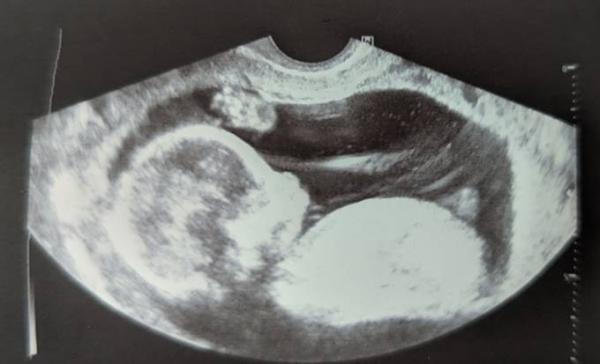

Hallo ihr lieben, ich bin aktuell in der 16 SSW und heute konnte die Frauenärztin nichts äußern. Aber wir haben ein Bild mitbekommen. Ich bin total aufgeregt was es wird, natürlich freuen wir uns über beides, aber die Aufregung und wenn Geduld eine Schwäche ist haha macht raten und rätseln doch spaß. Gibt es hier welche die sich mit den Theorien auskennen? Dann würde ich mich über Tips sehr freuen. LG

Bild zu Nun oder Skull Theorie - Rätselfreunde? - Forum für Juni - Mamis

Hallo, ich kenn mich zwar nicht aus aber würde auf ein Mädchen tippen. Das Ultraschallbild von meiner Tochter damals sah ähnlich aus LG

Ja, meine Vermutung geht auch Richtung Mädchen. Beim ersttrimesterscreening hat man zwischen den beinen gar nichts gesehen, auch nichts das für einen jungen sprach und da war ich in der 14 SSW. Ich bin so gespannt hihi